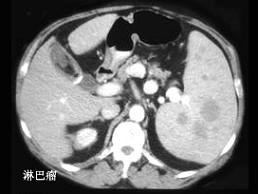

选项 A、脾脏脓肿 B、脾血管瘤 C、肝硬化并发脾肿大 D、某些血液疾病 E、外伤性脾破裂

答案 ABCDE